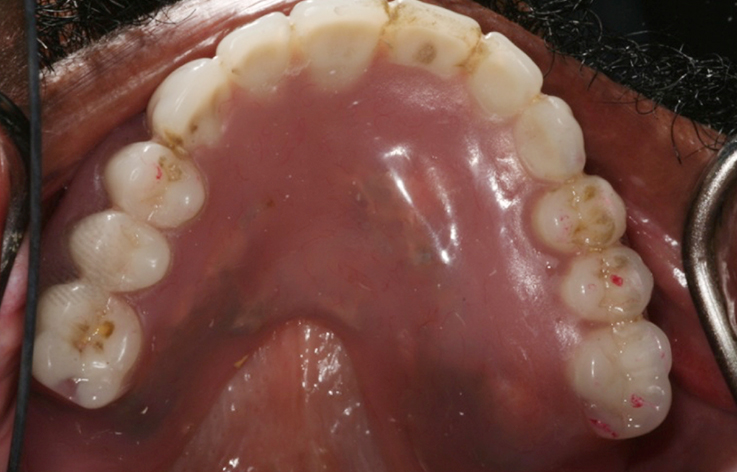

Fully edentulous clinical cases